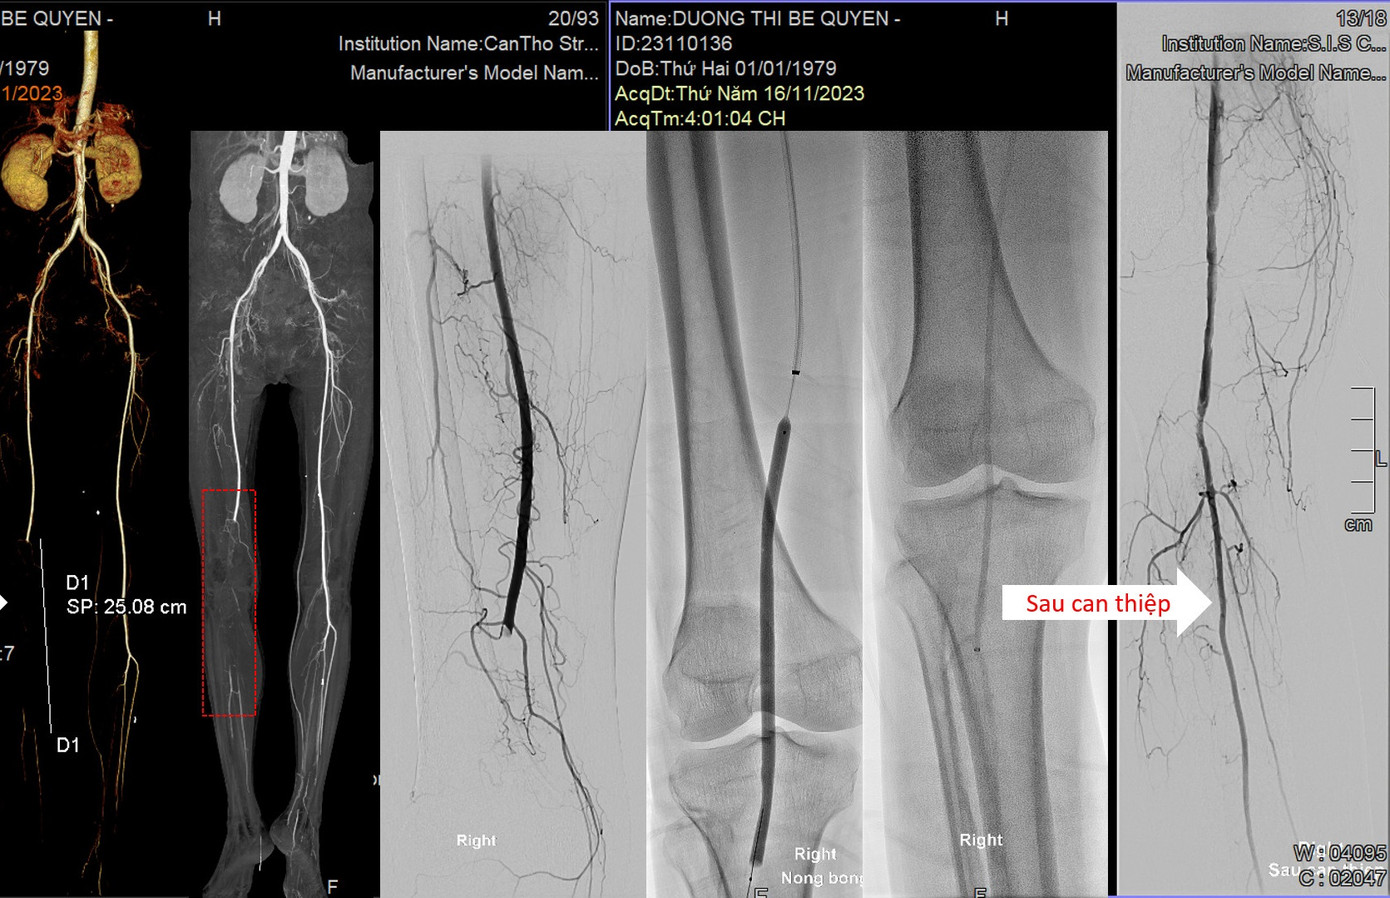

| Hình ảnh mạch máu của bệnh nhân bị tắc, sau khi can thiệp đã được tái thông |

Trước hoàn cảnh khó khăn trên, bệnh viện đã quyết định vận động hỗ trợ kinh phí từ các y bác sĩ và cộng đồng để điều trị cho bệnh nhân. Sau hơn 2 giờ nỗ lực can thiệp, các bác sĩ đã hút ra rất nhiều huyết khối được từ đoạn mạch máu dài hơn 20cm phần dưới đùi đến dưới gối phải. Ngay sau khi can thiệp, chân phải của bệnh nhân đã hồng hào trở lại, thoát khỏi nguy cơ nhiễm trùng, hoại tử.